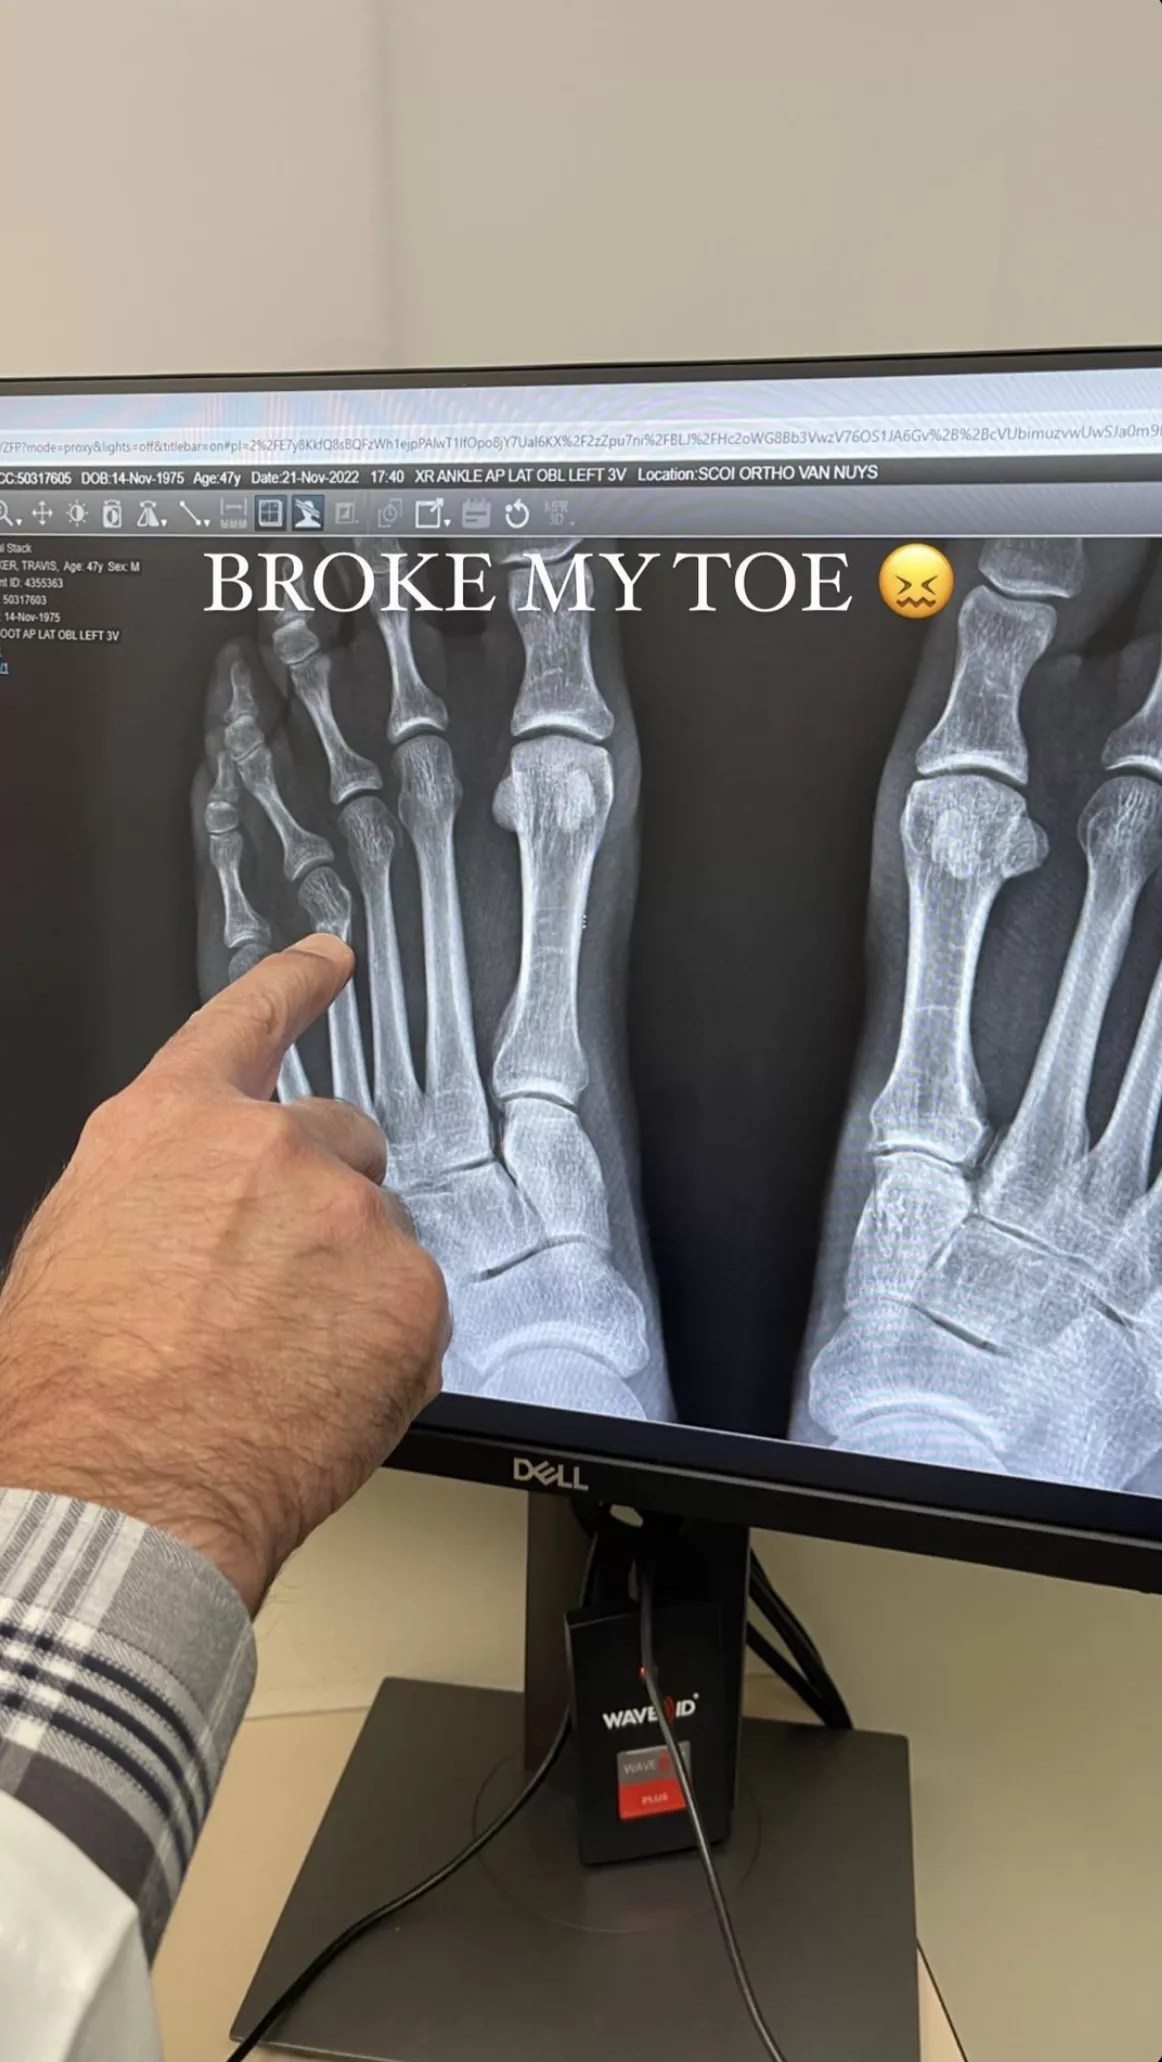

Travis Barker’s x-ray.Travis Barker Instagram Story

He also shared a photo of his x-ray on his Instagram Stories and wrote, “BROKE MY TOE.” In the next slide, he showed a photo of his walking boot.